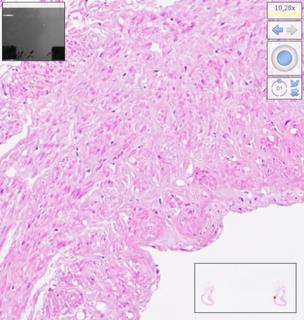

Histological examination was performed on days 7, 14, 21, 28, 35, 42, 49, 56, 63, 70, 77, 84 after homograft collection, ten arterial and ten venous preparations respectively. Twelve comparison groups of arterial and venous homografts were obtained. One hundred twenty arterial and 120 venous specimens were studied. The number of myocyte nuclei in the middle layer of homografts was estimated using automatic counting in the Image-PRO Plus 6.0 program (Figure 1) and recalculation of the obtained values per 0.01 mm2 (10,000 μm2) of the area of the middle layer of the vessel homograft wall. Counting was performed in 1 field of view at medium magnification (×100) using digital processing to visualize muscle cell nuclei. The software used was NDP.view2 (U12388-01; Hamamatsu Photonics KK).

Fig. 1. The stages of digital processing of the homograph wall (magnified ×100).